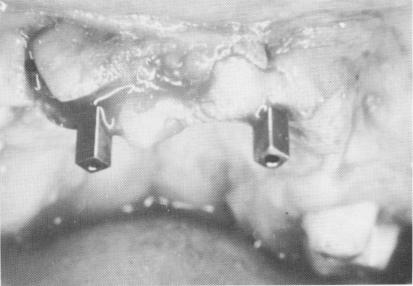

Fig. 15-15. Two narrow ridge type implants are then screwed into position.

Fig. 15-16. After healing around the two implants has been completed, the framework is cemented into position with hard cement.